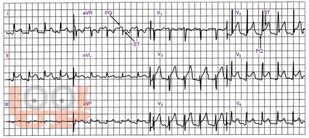

Изменения ЭКГ при некоторых заболеваниях и синдромах

Учебное пособие написано сотрудником кафедры функциональной диагностики ГБОУ ДПО КГМА Минздрава России. В пособии рассмотрены изменения ЭКГ при некоторых заболеваниях и синдромах, таких как острое легочное сердце, перикардит, миокардит, ожирение, дисгормональная кардиомиопатия, острое нарушение мозгового кровообращения и др. Освещены наиболее важные практические аспекты анализа ЭКГ в помощь врачам для проведения дифференциальной диагностики при различной патологии. Пособие предназначено для врачей функциональной диагностики, кардиологов и терапевтов.